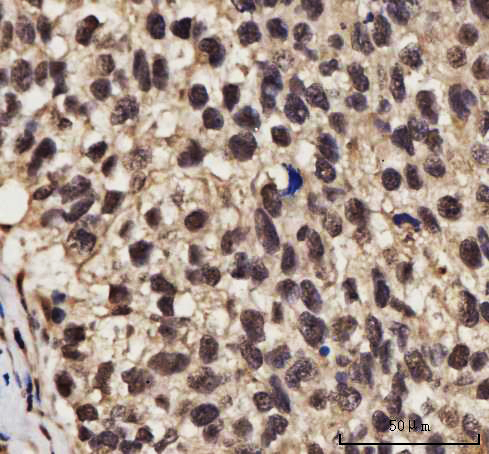

IHC (Immunohistochemisry)

(Figure 3. IHC analysis of NELFE using anti-NELFE antibody (AAA127423).NELFE was detected in a paraffin-embedded section of human ovarian cancer tissue. Heat mediated antigen retrieval was performed in EDTA buffer (pH 8.0, epitope retrieval solution). The tissue section was blocked with 10% goat serum. The tissue section was then incubated with 2ug/ml rabbit anti-NELFE Antibody (AAA127423) overnight at 4 degree C. Peroxidase Conjugated Goat Anti-rabbit IgG was used as secondary antibody and incubated for 30 minutes at 37 degree C. The tissue section was developed using HRP Conjugated Rabbit IgG Super Vision Assay Kit with DAB as the chromogen.)